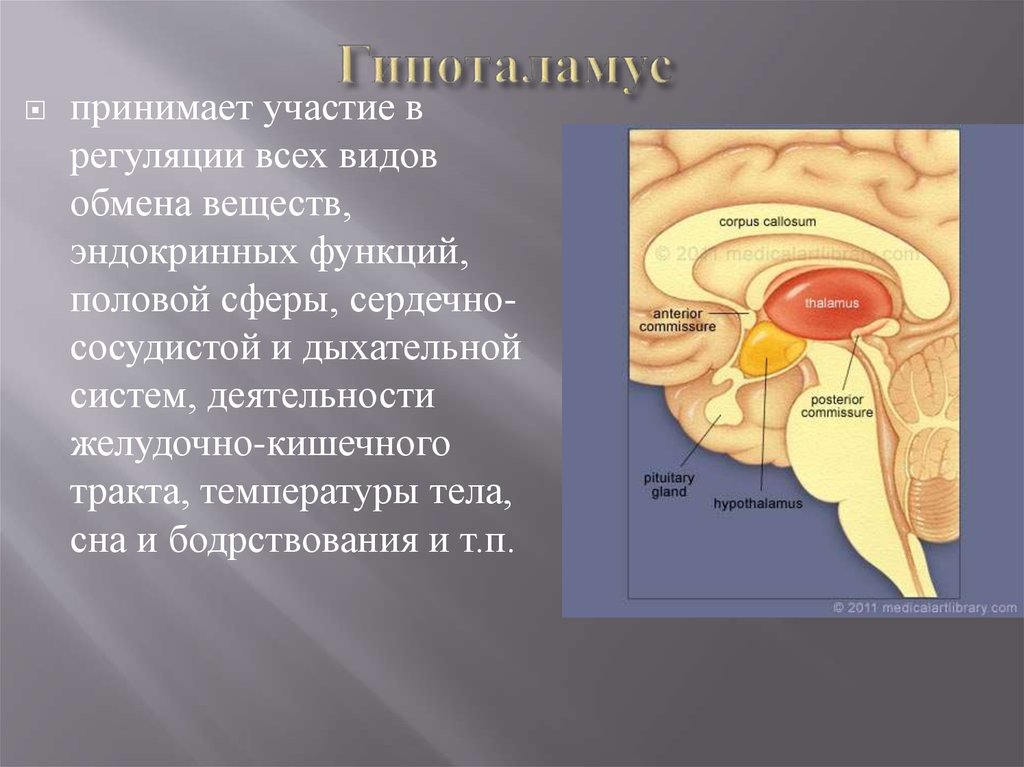

Как работает центр насыщения в гипоталамусе: визуальные иллюстрации